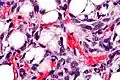

Histopathology of liposarcoma, H&E stain, with the main features:[5]

- Spindle cells with enlarged, hyperchromatic nuclei.

- Apparently univacuolated adipocytes (may look normal).

- Lipoblasts (multivacuolated), but neither necessary nor sufficient for diagnosis of liposarcoma. -

Lipoblasts are seen in liposarcoma[7] and characteristically have abundant multivacuolated clear cytoplasm and a dark staining (hyperchromatic), indented nucleus.